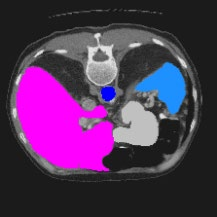

Transformers have made remarkable progress towards modeling long-range dependencies within the medical image analysis domain. However, current transformer-based models suffer from several disadvantages: (1) existing methods fail to capture the important features of the images due to the naive tokenization scheme; (2) the models suffer from information loss because they only consider single-scale feature representations; and (3) the segmentation label maps generated by the models are not accurate enough without considering rich semantic contexts and anatomical textures. In this work, we present CASTformer, a novel type of generative adversarial transformers, for 2D medical image segmentation. First, we take advantage of the pyramid structure to construct multi-scale representations and handle multi-scale variations. We then design a novel class-aware transformer module to better learn the discriminative regions of objects with semantic structures. Lastly, we utilize an adversarial training strategy that boosts segmentation accuracy and correspondingly allows a transformer-based discriminator to capture high-level semantically correlated contents and low-level anatomical features. Our experiments demonstrate that CASTformer dramatically outperforms previous state-of-the-art transformer-based approaches on three benchmarks, obtaining 2.54%-5.88% absolute improvements in Dice over previous models. Further qualitative experiments provide a more detailed picture of the model's inner workings, shed light on the challenges in improved transparency, and demonstrate that transfer learning can greatly improve performance and reduce the size of medical image datasets in training, making CASTformer a strong starting point for downstream medical image analysis tasks.